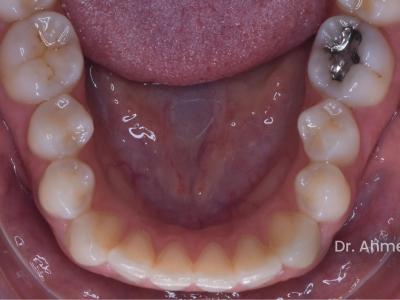

Missing UR2, to open the space for a future implant, half unit class II on the right side

Class II

28 Upper

25 Lower

Refinement Steps

24 lower